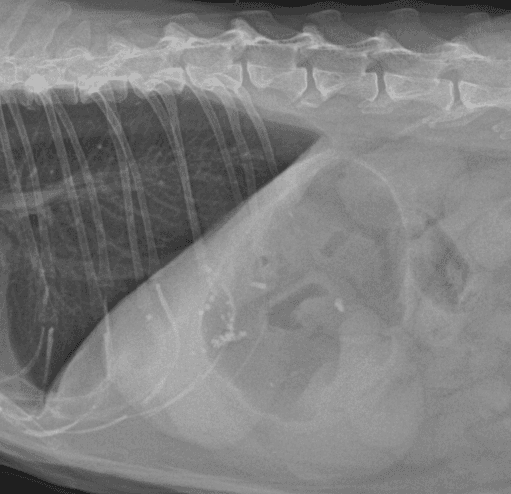

간, 담도 수술은 수술뿐만 아니라, 수술 후 중환자 관리도 중요하기 때문에 외과와 내과의 협진이 매우 중요합니다. 동탄시티동물의료센터에서는 최신 수술 장비의 도입으로 간담도 수술에서 출혈 및 부작용을 최소화 하였으며, 수술 후 협진 시스템을 통해 수술 후 관리에도 최선을 다하고 있습니다.

간종양

담석

담낭점액종